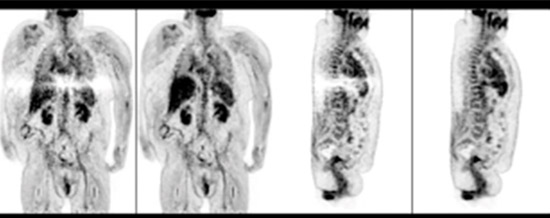

Time-of-Flight-Rekonstruktion anhand von SSS mit Tail-Fitting (jeweils linkes Bild des Bildpaars) und ×Clean (jeweils rechtes Bild). Die Artefakte, die bei der SSS mit Tail-Fitting auftreten, treten bei den ×Clean-Rekonstruktionen nicht auf.

Bild mit freundlicher Genehmigung der University of Pennsylvania School of Medicine, Philadelphia, USA